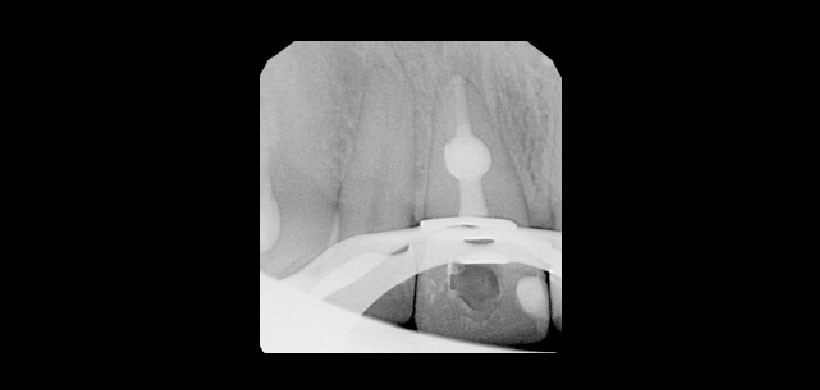

Figura 3: Tratamiento de conductos en una pieza 11 con reabsorción interna tipo B.